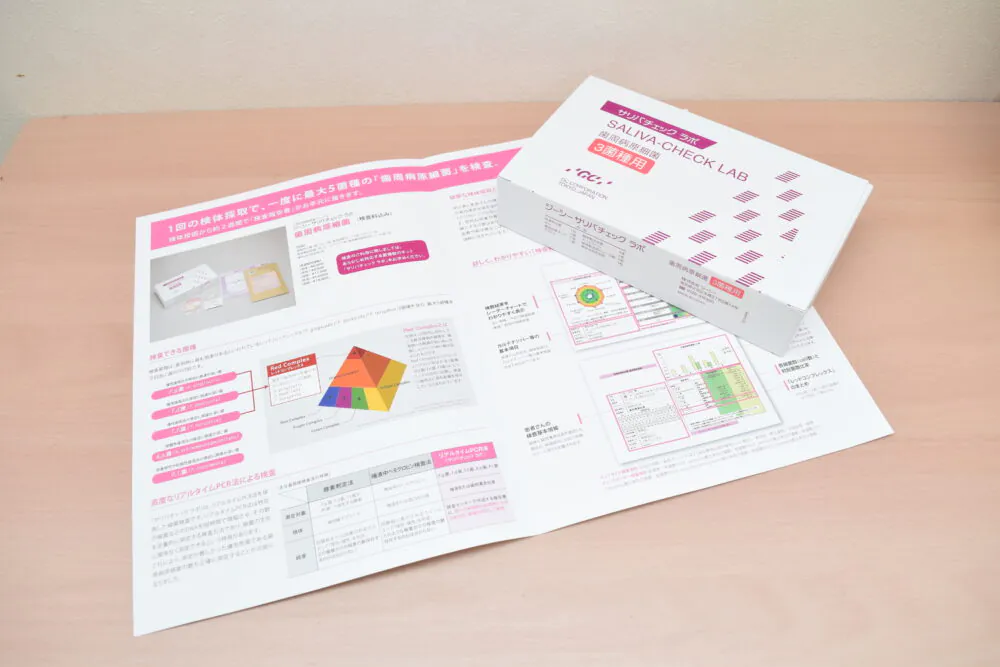

歯周細菌検査

位相差顕微鏡を用いた口腔内の細菌検査は、歯周病の進行を抑制し、再発を減少させるための効果的な手段です。口腔内には約500~700種類の細菌が生息しており、これらの細菌の種類や数、活動性を位相差顕微鏡で観察することができます。歯に付着したプラークを採取し、位相差顕微鏡にセットして高倍率で観察します。歯周病菌の存在を確認し、治療の方針を立てることが可能です。検査は約10分で終わり、即座に診断が可能です。

位相差顕微鏡を用いた口腔内の細菌検査は、歯周病の進行を抑制し、再発を減少させるための効果的な手段です。口腔内には約500~700種類の細菌が生息しており、これらの細菌の種類や数、活動性を位相差顕微鏡で観察することができます。歯に付着したプラークを採取し、位相差顕微鏡にセットして高倍率で観察します。歯周病菌の存在を確認し、治療の方針を立てることが可能です。検査は約10分で終わり、即座に診断が可能です。